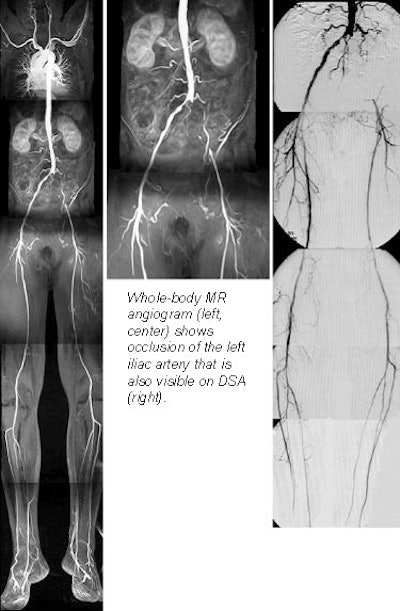

A new rolling-platform table could make whole-body MR angiography fast and practical for the first time, according to Dr. Mathias Goyen, a radiologist from University Hospital Essen in Germany. AngioSURF's ability to reduce procedure times and increase anatomical coverage has made it popular with both patients and clinicians at the university's MR center, where the table was developed.

In two studies presented at last month's European Congress of Radiology, Goyen and colleagues evaluated AngioSURF's performance, and sought to determine the optimal contrast dose needed to detect pathology in the peripheral vessels. Users of the system were not only able to detect significant pathology, but its longer coverage helped them find unsuspected disease as well.

"Recently, whole-body MR angiography has become possible by combining the contrast-enhanced MRA approach with the latest high-performance gradients," Goyen said. "We are now able to (image) the arteries from the carotids down to the runoff vessels in a single exam. Our preliminary results are quite promising, with sensitivities and specificities for detecting stenoses and occlusions in the mid-80s up to the mid-90s."

The first study examined 3 healthy volunteers, as well as 10 patients with angiographically documented peripheral vascular disease. The patients had all undergone digital subtraction angiography (DSA) within the previous 72 hours. Evaluation of the AngioSURF system was based on a total of 214 vascular segments for which DSA was available for comparison.

The results were based on 214 vascular segments in which DSA was available for comparison. All patients tolerated the exams well, and all exams were of diagnostic quality, showing complete correlation with DSA findings, Goyen said. For the detection of significant stenoses, the AngioSURF procedures had a sensitivity of 95.3% and specificity of 95.2% compared to DSA.

"The AngioSURF system allowed the accurate display of arteriovasculature from the supraaortic arteries to the lower extremity vessels," Goyen said. "Due to the extended coverage that's provided, we found additional findings that may be relevant to the treatment and diagnosis of vascular disease."